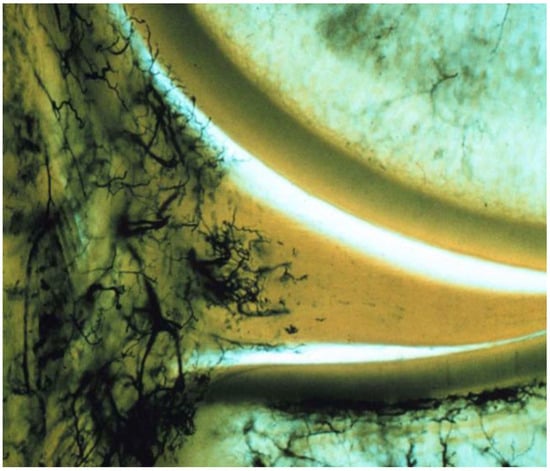

The evidence clearly demonstrates that the meniscus has limited vascularity, with blood vessels primarily confined to the outer (peripheral) region. Multiple anatomical and histological studies show that in adults, vascular penetration typically reaches only the outer 10–33% of the meniscus, while the inner two-thirds remain largely avascular [4,5,6]. For example, Crawford et al. found that in young adults, the maximal depth of vascular penetration ranged from 0% to 42% in the medial meniscus and 0% to 48% in the lateral meniscus, with the posterior horn of medial meniscus being the least vascularized [4]. Michel et al. further quantified that after adolescence, no blood vessels are found in the inner (white-white) and intermediate (red-white) zones, and almost all vessels are located only in the capsule or outermost region [5]. Representative histologic images from the classic vascular mapping study by Arnoczky and Warren illustrate that vascular penetration is largely restricted to the peripheral one-third of the meniscus [7] (Figure 1). This limited vascularity of the meniscus, especially in the inner zones, is a key reason for its poor intrinsic healing capacity after injury.

Figure 1. Histologic demonstration of meniscal vascularity showing blood supply confined predominantly to the peripheral one-third of the medial meniscus. Reproduced with permission from Arnoczky and Warren [7], The American Journal of Sports Medicine, 1982.